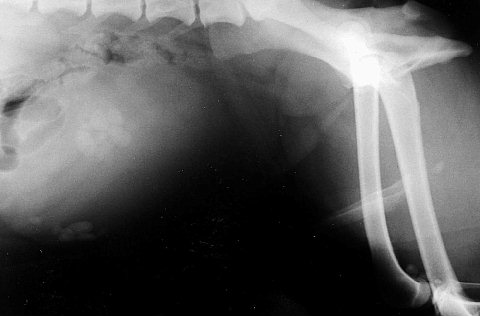

こちらは大きい結石がありますね。

もう一つ珍しい結石を・・・

これはケイ素を主成分とするケイ酸結石です。

これ自体が珍しいのに、通常は5mm程度の小さなものらしいのですがこれは大きかったですね。

これはレントゲンに映るんですが、骨盤骨折の疑いで撮ったレントゲン検査で偶然発見して手術したものです。